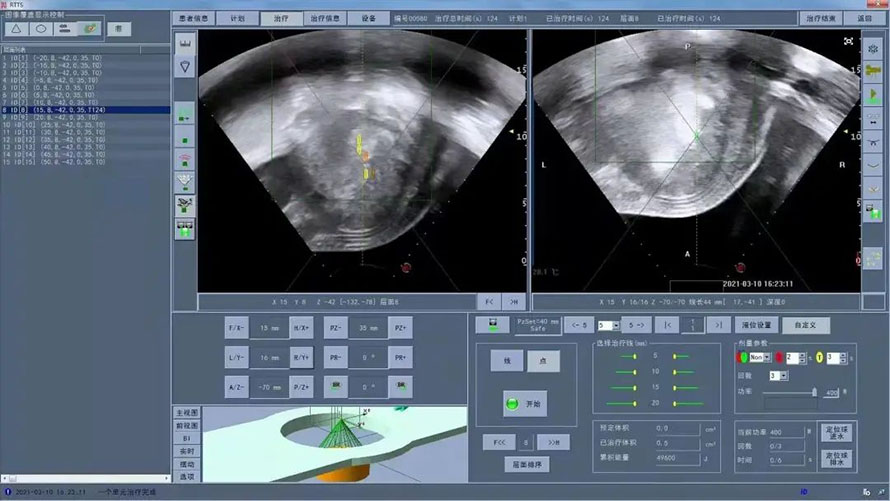

The operation was carried out on time, because the operation was carried out in a fully awake state, Xiaoxiao sobbed softly, or lamented the injustice of fate, or thanked God for opening another door for her. Her crying seemed to be a release of life, but fortunately, the result of the operation that day was good, and there was hope of life.